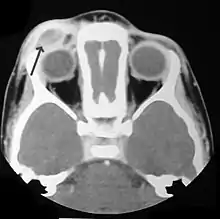

CT scan showing LCH infiltrating peri-orbital tissue (arrowed).